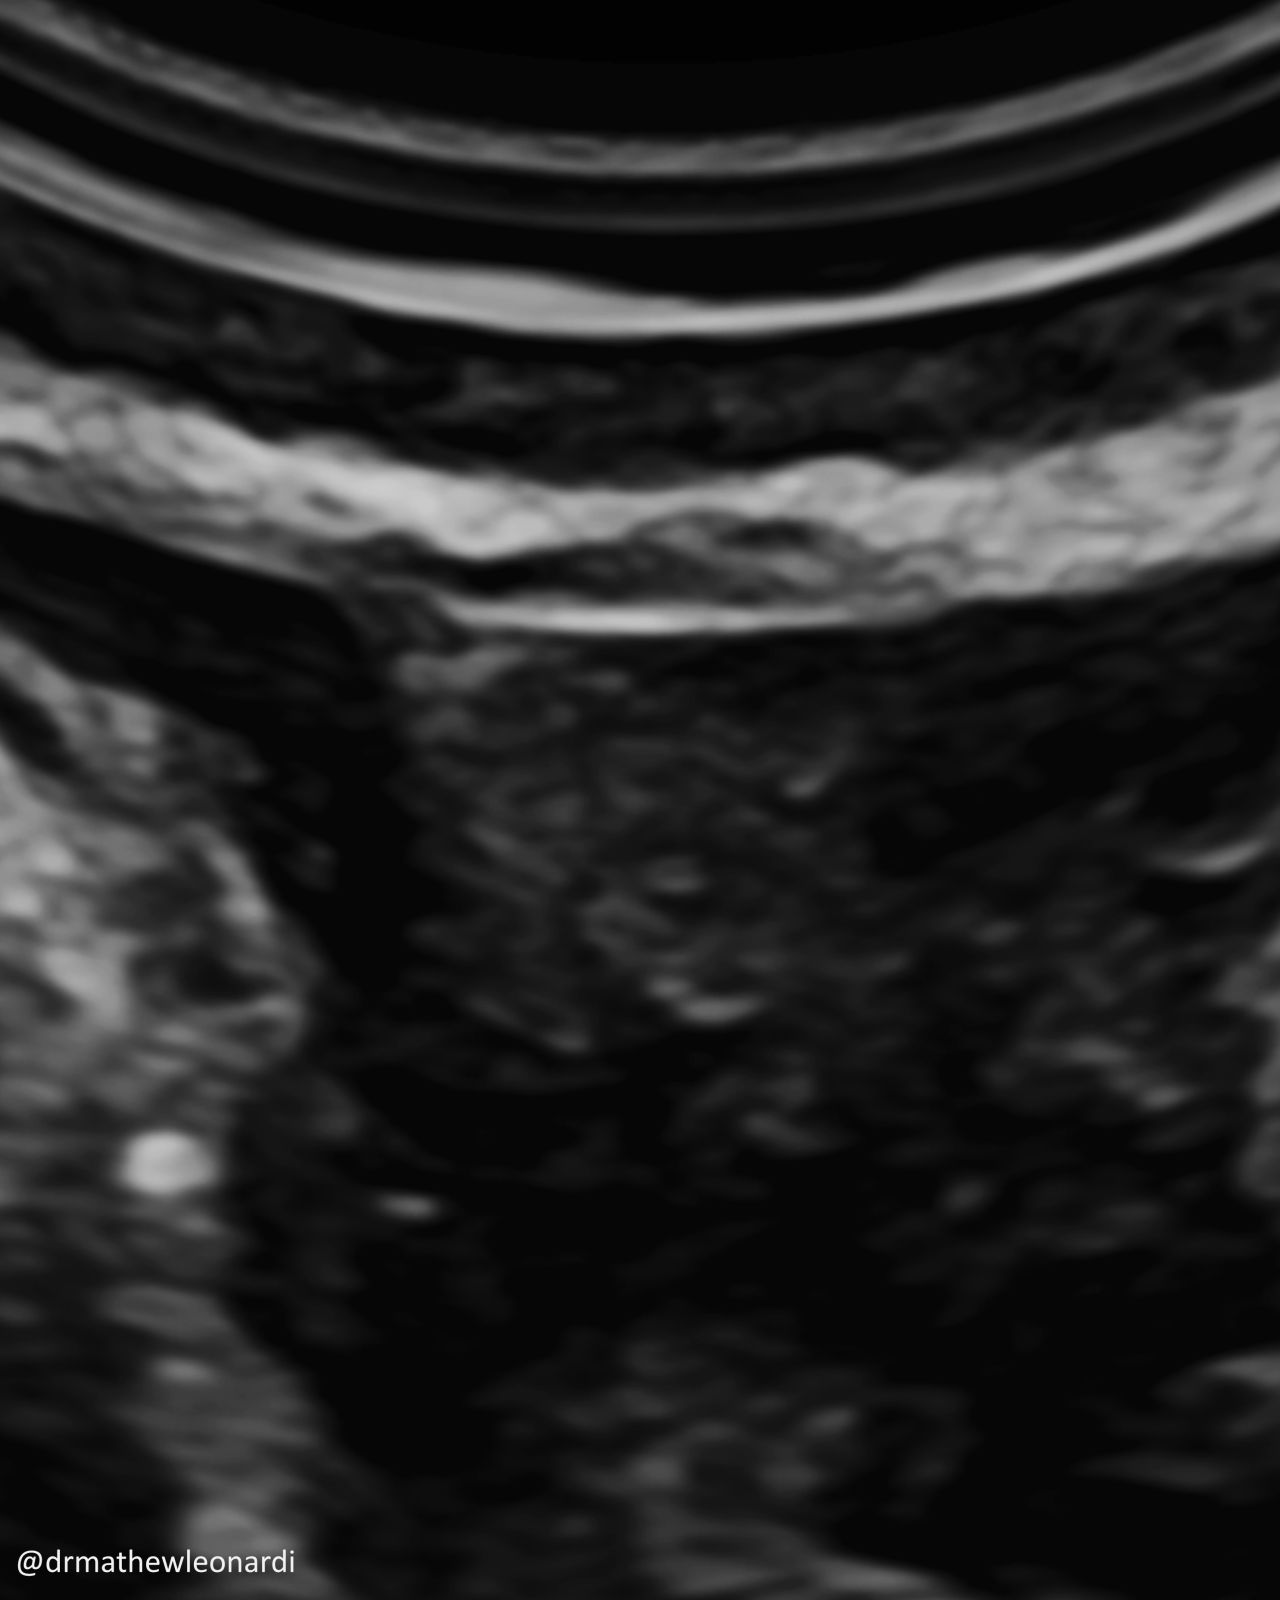

“Endometriosis does not have one single appearance, and that is part of why it is so often missed.

In this carousel, I’ve included a range of endometriosis lesions across different disease types and locations, including superficial disease, ovarian disease, and deep endometriosis involving areas such as the bowel, bladder, uterosacral ligaments, peritoneum, vagina, and ovary. A few are deliberately difficult because real-life recognition is not always straightforward.